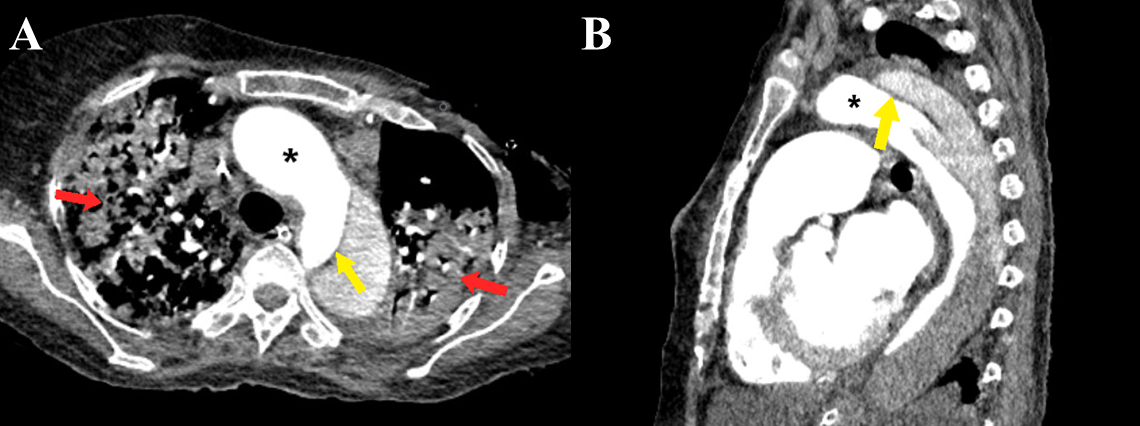

Figure 8 a-b Stanford type B aortic dissection. Axial (a) and sagittal (b) CT angiography images show the dissection flap (yellow arrows) involving the descending thoracic aorta distal to the origin of the left subclavian artery. Large consolidations are also evident in bilateral lungs (red arrows). Note the greater enhancement within the true lumen as compared to the false lumen (black asterisk).

The Stanford classification divides aortic dissections into 2 types: Stanford type A involves the aorta proximal to the origin of the left subclavian artery (i.e., ascending aorta or aortic arch), irrespective of descending aortic involvement (Figures 5a & 5b). It may involve the great vessels (Figure 6). Stanford type B involves the aorta distal to the origin of the left subclavian artery (Figure 7) (Figures 8a-8b). Stanford type B can be managed medically, but Stanford type A needs urgent surgical repair to avoid life-threatening complications. Stanford type A corresponds to DeBakey types I and II while Stanford type B corresponds to DeBakey type III.6,9,14 Stanford type A (DeBakey type I and II) aortic dissections are more common, accounting for two-thirds of cases. They require urgent surgical repair as they have a mortality rate of 1% to 2% per hour after the onset of symptoms. Stanford type B (DeBakey type III) aortic dissections are usually managed conservatively, in the absence of any complications.2,5,6,9,17